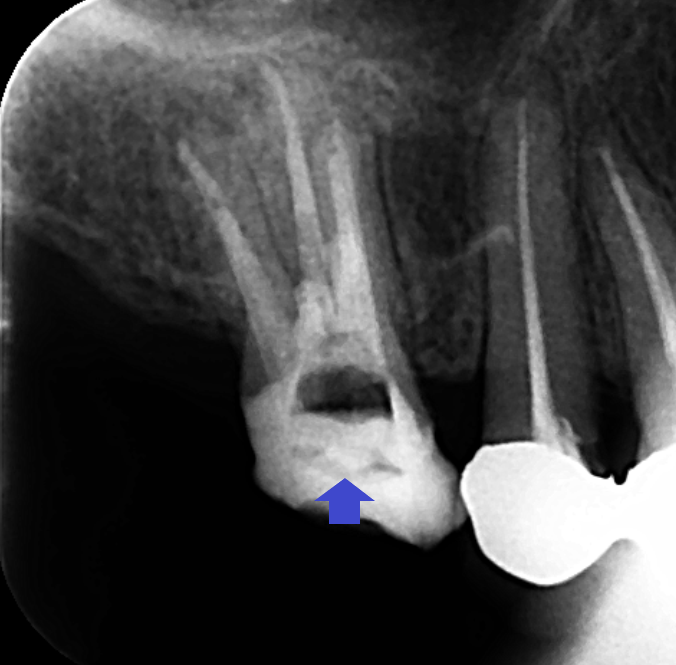

精密再根管治療とパーホレーションリペアを行いました。画像は、根管充填とパーホレーションリペア時のレントゲン画像です。